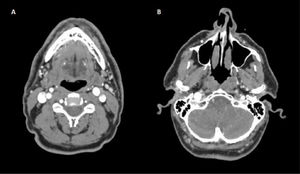

Se completa el estudio con una analítica básica, siendo el hemograma, coagulación y bioquímica incluyendo perfil hepático e iones normales. En la radiografía de tórax no se detectan masas ni ocupación del ápex pulmonar derecho. La TC de cráneo es normal y la angioTC de arterias supraaórticas descarta patología carotídea; sin embargo, se describe una prominencia del golfo de la vena yugular derecha, sin dehiscencia de la lámina ósea, con un foramen yugular prominente (fig. 1). Se completa el estudio con una RM craneal (fig. 2) y medular hasta T1 con contraste, sin detectarse patología a nivel de la vía simpática. Los marcadores tumorales, serología lúes, VIH y Borrelia han sido negativos. Se ha completado el estudio con una TC torácica que descarta patología compresiva o mediastínica.

Describimos el caso de un paciente con antecedentes de hipoacusia neurosensorial súbita derecha y tinnitus derecho que presenta años después un síndrome de Horner ipsilateral. En el estudio de imagen se describe un golfo yugular prominente con una asimetría en el calibre de ambas venas yugulares. Observamos en las pruebas de imagen un contacto de la vena yugular derecha (que es más gruesa respecto a la contralateral) con la arteria carótida interna derecha previo a la entrada en el foramen yugular, que podría originar una compresión de la vía simpática a este nivel. Dados los antecedentes del paciente y el estudio de imagen actual, creemos que podrían ser el origen de los síntomas del paciente, en ausencia de otra patología que actualmente lo pueda justificar.